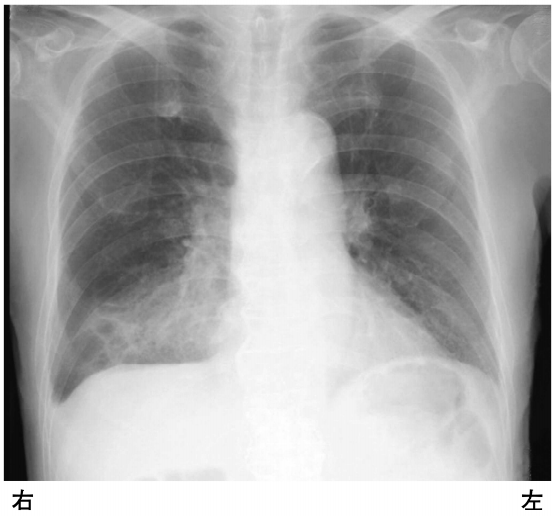

トップ 医療・介護・福祉に関する資格 理学療法士 平成29年度 第52回 過去問(2017年度) 問0 全部で189問 挑戦中 午前 問題 嚥下障害がある患者の胸部エックス線写真を別に示す。 予想される理学所見はどれか。 (1) 胸痛 乾性咳嗽 頸静脈怒張 右胸部打診で鼓音 右胸部聴診で水疱音 次の問題へ